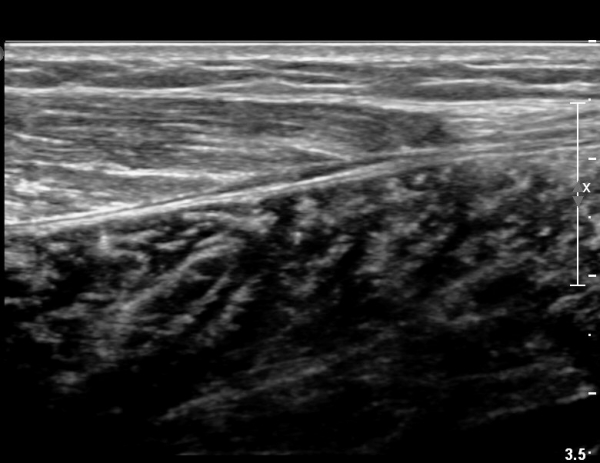

[¹ß¸ñ] simultaneosus tear of GCM and achiles tendon

abrupt leg pain developed during foot volleyball

he walk with severe limping with no weight bearing on rt. leg. on examination, there is local tendernes at GCM and achiles tendon, severe pain with ankle dorsiflexion.

ÃÊÀ½ÆÄ °Ë»ç